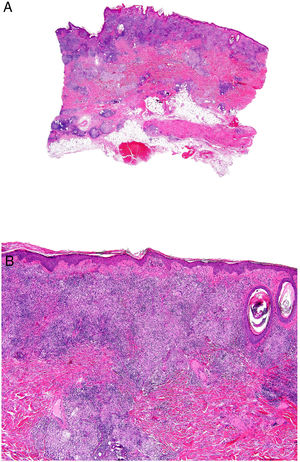

Histopatología: Infiltrado dérmico difuso de linfocitos atípicos de pequeño tamaño (inmunofenotipo T helper: CD3+, CD4+ y CD8−), que puede extenderse a hipodermis (figs. 15B y C), con numerosas células gigantes multinucleadas (figs. 16A y B) que muestran elasto- y linfo-fagocitosis (figs. 16C y D). En fases iniciales, la histología puede ser similar a una micosis fungoide convencional. Con PCR se demuestra reordenamiento del receptor de célula T (TCR)34.

Piel laxa granulomatosa. A) Infiltración linfoide en dermis con numerosas células gigantes multinucleadas salpicadas (H&E ×40). B) Infiltración linfoide en septos de la hipodermis con células gigantes multinucleadas (H&E ×40). C) Detalle de una célula gigante con linfofagocitosis (H&E ×200). D) Fragmentación y pérdida de fibras elásticas (orceína ×100).